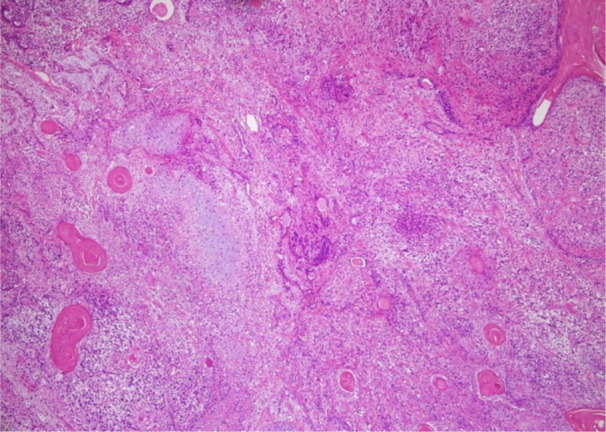

肺癌肉瘤是一种罕见的由非小细胞癌和肉瘤成分组成的肿瘤,大多数病例分化较差。我们报告一例具有分化良好的癌性成分的癌性肉瘤,需要与畸胎瘤衍生的肿瘤进行鉴别诊断,如畸胎瘤癌性肉瘤。我们提出一个68岁的男性病例,他到我们医院检查一个22毫米的肺肿瘤。患者行左侧S1+2节段切除术,术后过程平稳。术后21个月随访未见复发。节段切除术标本显示一个黄白色、边界清楚的肿块。肿瘤包括分化良好的鳞状上皮和腺状上皮,以及未成熟梭形细胞、软骨肉瘤和横纹肌肉瘤的肉瘤成分。病人被诊断为癌肉瘤。本病例包含分化良好的癌成分,有必要将其与畸胎瘤肉瘤区分开来。没有神经成分,没有在畸胎癌肉瘤中观察到的SMARCA4丢失,排除了畸胎癌肉瘤。癌肉瘤的特点是双期组织病理学模式,这使得很难在活检中准确诊断,活检只能捕获肿瘤的一部分。即使术前活检怀疑畸胎瘤衍生的肿瘤,也应考虑癌肉瘤的可能性。

Pulmonary carcinosarcoma is a rare tumor composed of non-small-cell carcinomas and sarcomatous elements, which is poorly differentiated in most cases. We present a case of carcinosarcoma with a well-differentiated carcinomatous component that required a differential diagnosis from tumors derived from teratomas, such as teratocarcinosarcoma. We present a case of a 68-year-old man who visited our hospital for an examination of a 22-mm lung tumor. The patient underwent left S1+2 segmentectomy, and his postoperative course was uneventful. No recurrence was observed in the 21-month postoperative follow-up period. The segmentectomy specimen revealed a yellow-white, well-circumscribed mass. The tumor consisted of well-differentiated squamous and glandular epithelia, and sarcomatous components of immature spindle cells, chondrosarcoma, and rhabdomyosarcoma. The patient was diagnosed with carcinosarcoma. This case included well-differentiated carcinomatous components, and it was necessary to differentiate it from teratocarcinosarcomas. There was no neural component, and without SMARCA4 loss, which is observed in teratocarcinosarcoma, and ruled out teratocarcinosarcoma. Carcinosarcomas are characterized by a biphasic histopathological pattern, making it difficult to accurately diagnose them on biopsy, which only captures a portion of the tumor. The possibility of carcinosarcoma should be considered even when the tumors derived from teratomas are suspected on preoperative biopsy.